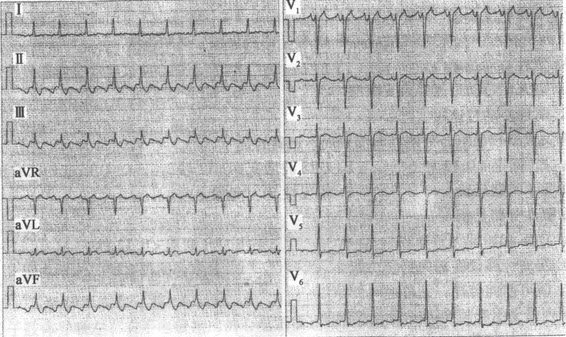

患者女性,26岁,偶发胸闷、心悸。心电图如图所示,应诊断为()

A.窦性心律不齐